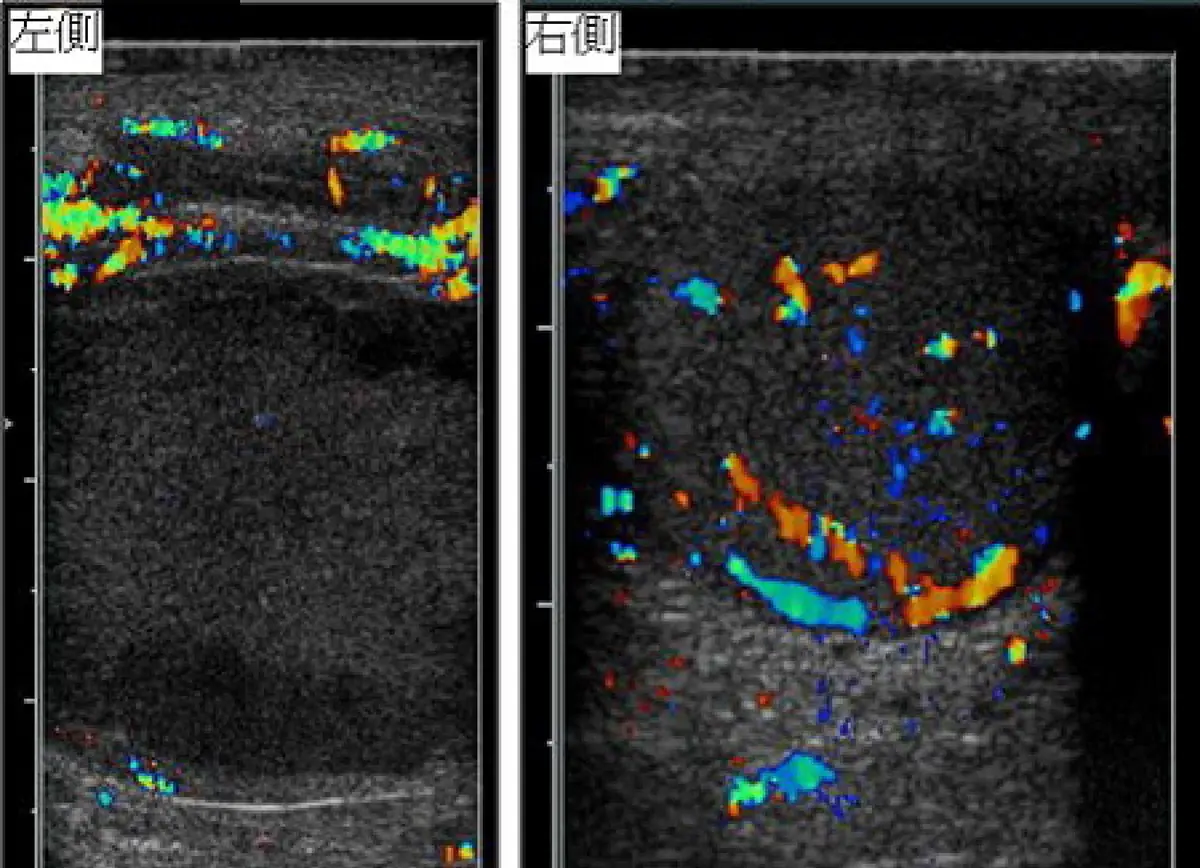

附圖為陰囊突然劇痛 10 歲男孩之陰囊都卜勒超音波掃描,最可能的診斷為何?

本題附圖為雙側陰囊彩色都卜勒超音波對照影像:

- 左側(左側標示):睪丸呈均勻低回音實質,睪丸內完全無彩色血流訊號,僅可見皮膚/陰囊壁少量表淺血流。睪丸實質缺乏灌流,為缺血改變。

- 右側(右側標示):睪丸內可見豐富的橘紅色及藍色血流訊號,分佈均勻,代表正常睪丸動靜脈灌流。

影像判讀結論:左側睪丸血流消失、右側血流正常 → 此為睪丸扭轉的典型都卜勒表現,病灶位於左側。